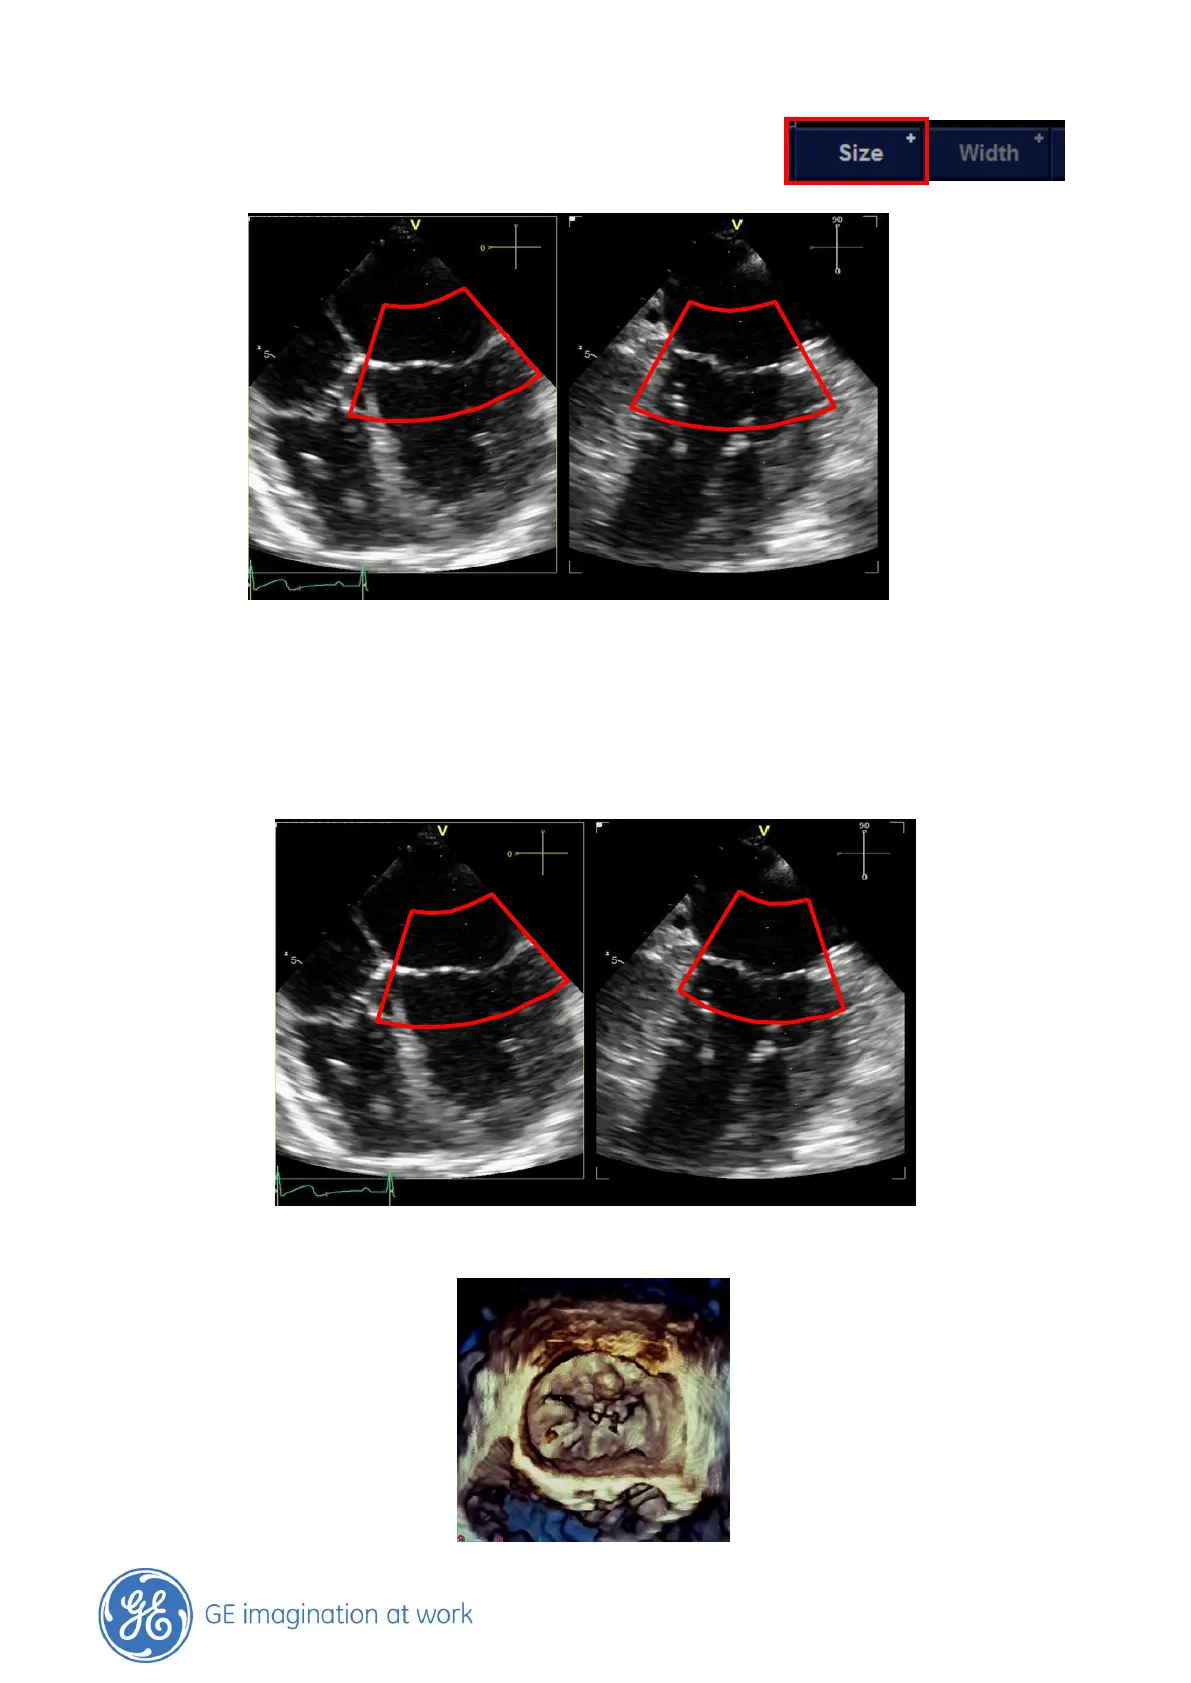

Press the Set button to change from Position to ROI Size and

adjust accordingly.

Use the Set button to change between Position and Size and optimize until satisfied.

To further adjust in Elevation plane, press the Trackball button or use the Ref Plane button on the

touch panel.

Adjust Width and Position in the elevation plane (switch between those two functions with Set

button)

Finally when ready with the adjustments press the 4D Button to start the 4D Zoom Acquisition